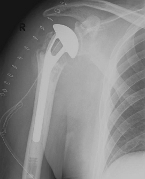

Abbildung11(2)Abbildung11

Fracture prostheses for complicated humeral head fractures

left: X-ray of a humeral head fracture before treatment with a fracture prosthesis.

right: X-ray of a humeral head fracture after treatment with a fracture prosthesis